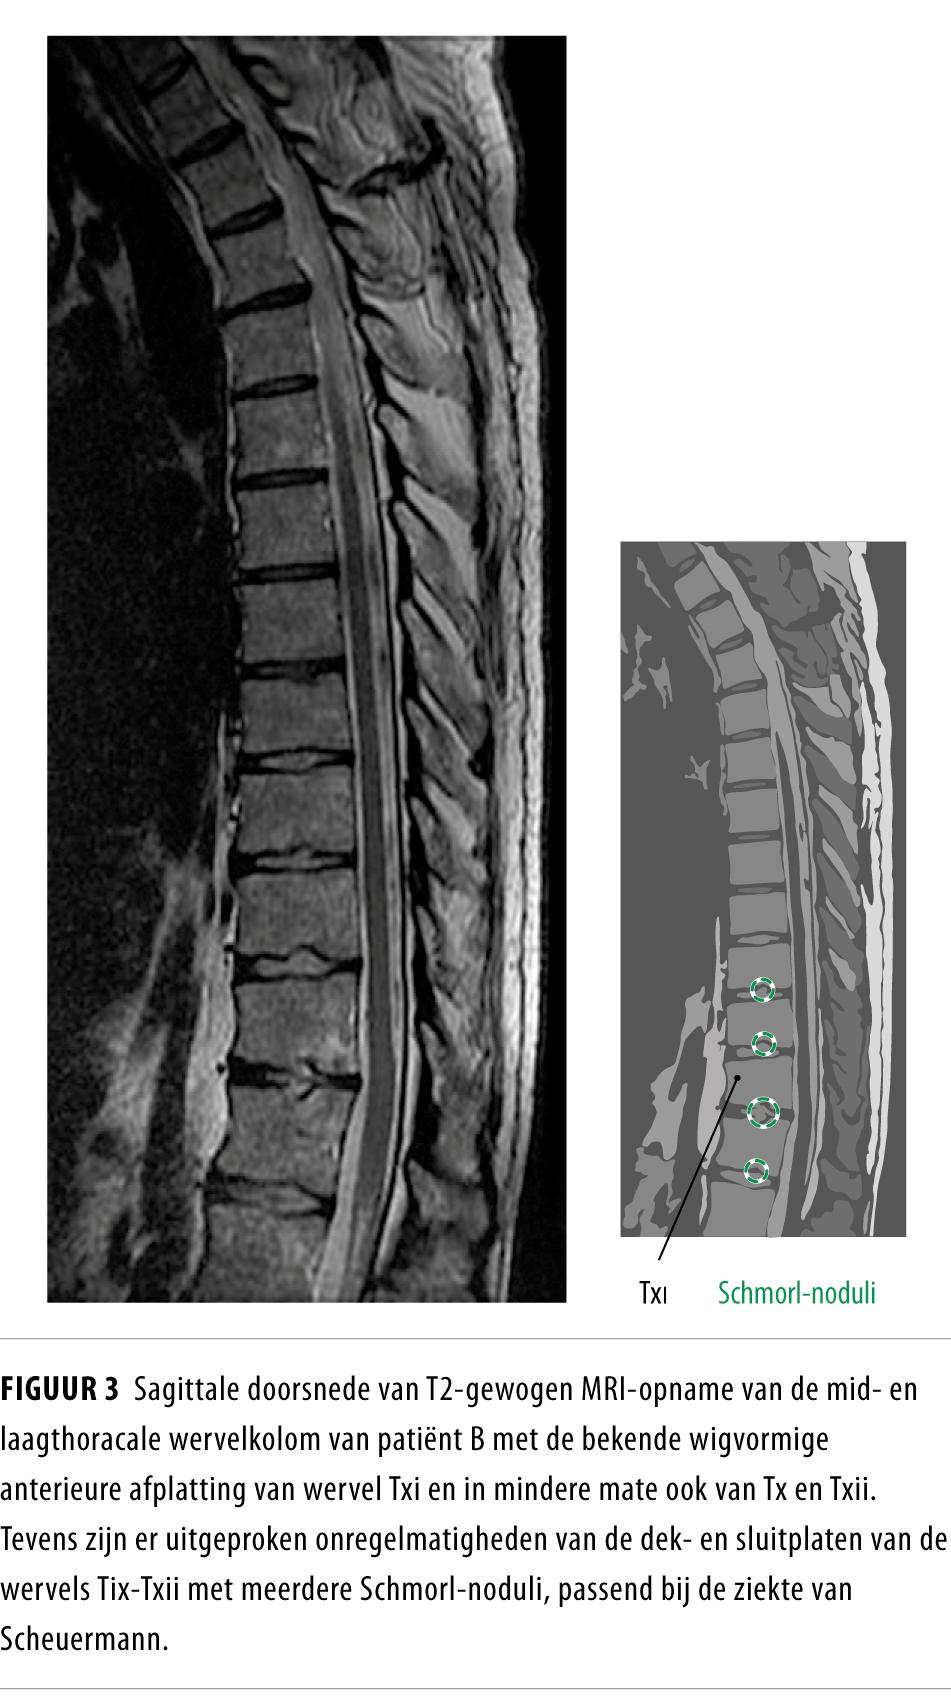

Laboratoriumonderzoek toonde geen aanwijzingen voor secundaire osteoporose. Een DEXA-scan toonde onverwacht een hoge botdichtheid van de lumbale wervels (+3,4 SD) en een normale botdichtheid van de heup (-0,1 SD). Vanwege de sterke discrepantie tussen de rugklachten, de risicofactoren en wervelinzakkingen enerzijds, en de hoog-normale botdichtheid anderzijds, lieten we een MRI-scan van de wervelkolom verrichten. De bevindingen op deze scan leken eerder te passen bij de ziekte van Scheuermann dan bij osteoporotische wervelfracturen (figuur 3). Er was dus geen indicatie voor medicamenteuze behandeling van osteoporose of voor het verrichten van een vertebroplastiek. In retrospect waren ook op de röntgenfoto Schmorl-noduli zichtbaar, echter niet zo duidelijk als bij patiënt A.

Figuur 3